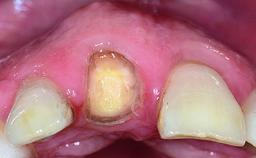

A healthy 37-year-old female patient was referred for a consultation on the replacement of missing tooth 21 with an implant-supported restoration. She stated that several years previously the tooth had been traumatically avulsed following a motor vehicle accident. The tooth was replaced with a three-unit fixed partial denture (FPD) immediately afterwards. Over time, she became disillusioned with the FPD and looked for a different option, including orthodontic therapy. She presented still in her orthodontic appliances, with the pontic sectioned free from the FPD but attached to the archwire. Her orthodontist felt that orthodontic treatment had been successfully completed, but nevertheless referred her before removing the appliances in case adjustments were necessary.

| Abutment Type | CAD/CAM |